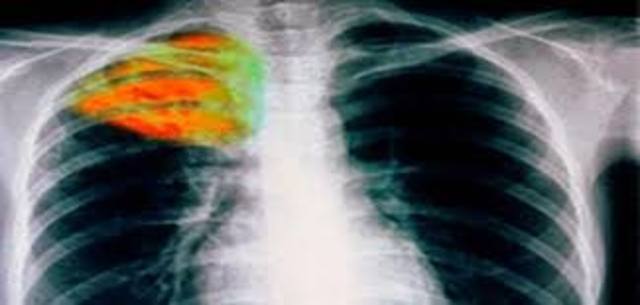

Το εμβόλιο εναντίον της Φυματίωσης από το 1927 που ανακαλύφθηκε χορηγείται συστηματικά σαν ρουτίνα σε νεογέννητα σε πολλές χώρες ενώ σε άλλες χορηγείται σε ομάδες υψηλού κινδύνου. Παρ'όλo που σήμερα δεν βλέπουμε τις σοβαρές επιδημίες της νόσου που συνέβησαν το 1930-1940, εντούτοις η Φυματίωση εξακολουθεί να προσβάλλει χιλιάδες ανθρώπους κόσμο κάθε χρόνο.